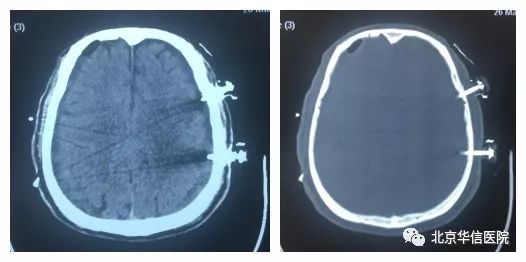

一位69岁老年男性患者,自诉2个月前骑自行车摔倒,近一个多月出现步态不稳,行走时右脚拖沓,并逐渐出现全身乏力及僵硬感。3月21日,患者来北京华信医院(清华大学第一附属医院)神经内科以帕金森综合征收住院治疗,通过头颅CT检查提示:双侧慢性硬膜下血肿,出血量很大,以左侧居多。于是转入神经外科治疗,完善头颅MR检查,明确诊断。期间患者症状逐渐加重,意识朦胧,急诊在全麻下行双侧慢性硬膜下血肿钻孔引流术,术中左侧引流出陈旧性血液量约80ml,右侧引流出陈旧性血液体量约40ml,术后患者右侧肢体活动明显好转,活动自如,意识很快清醒。持续引流2天后,复查头颅CT,血肿清除,术后第3天拔出穿刺针,患者目前已治愈出院。

术后头颅CT